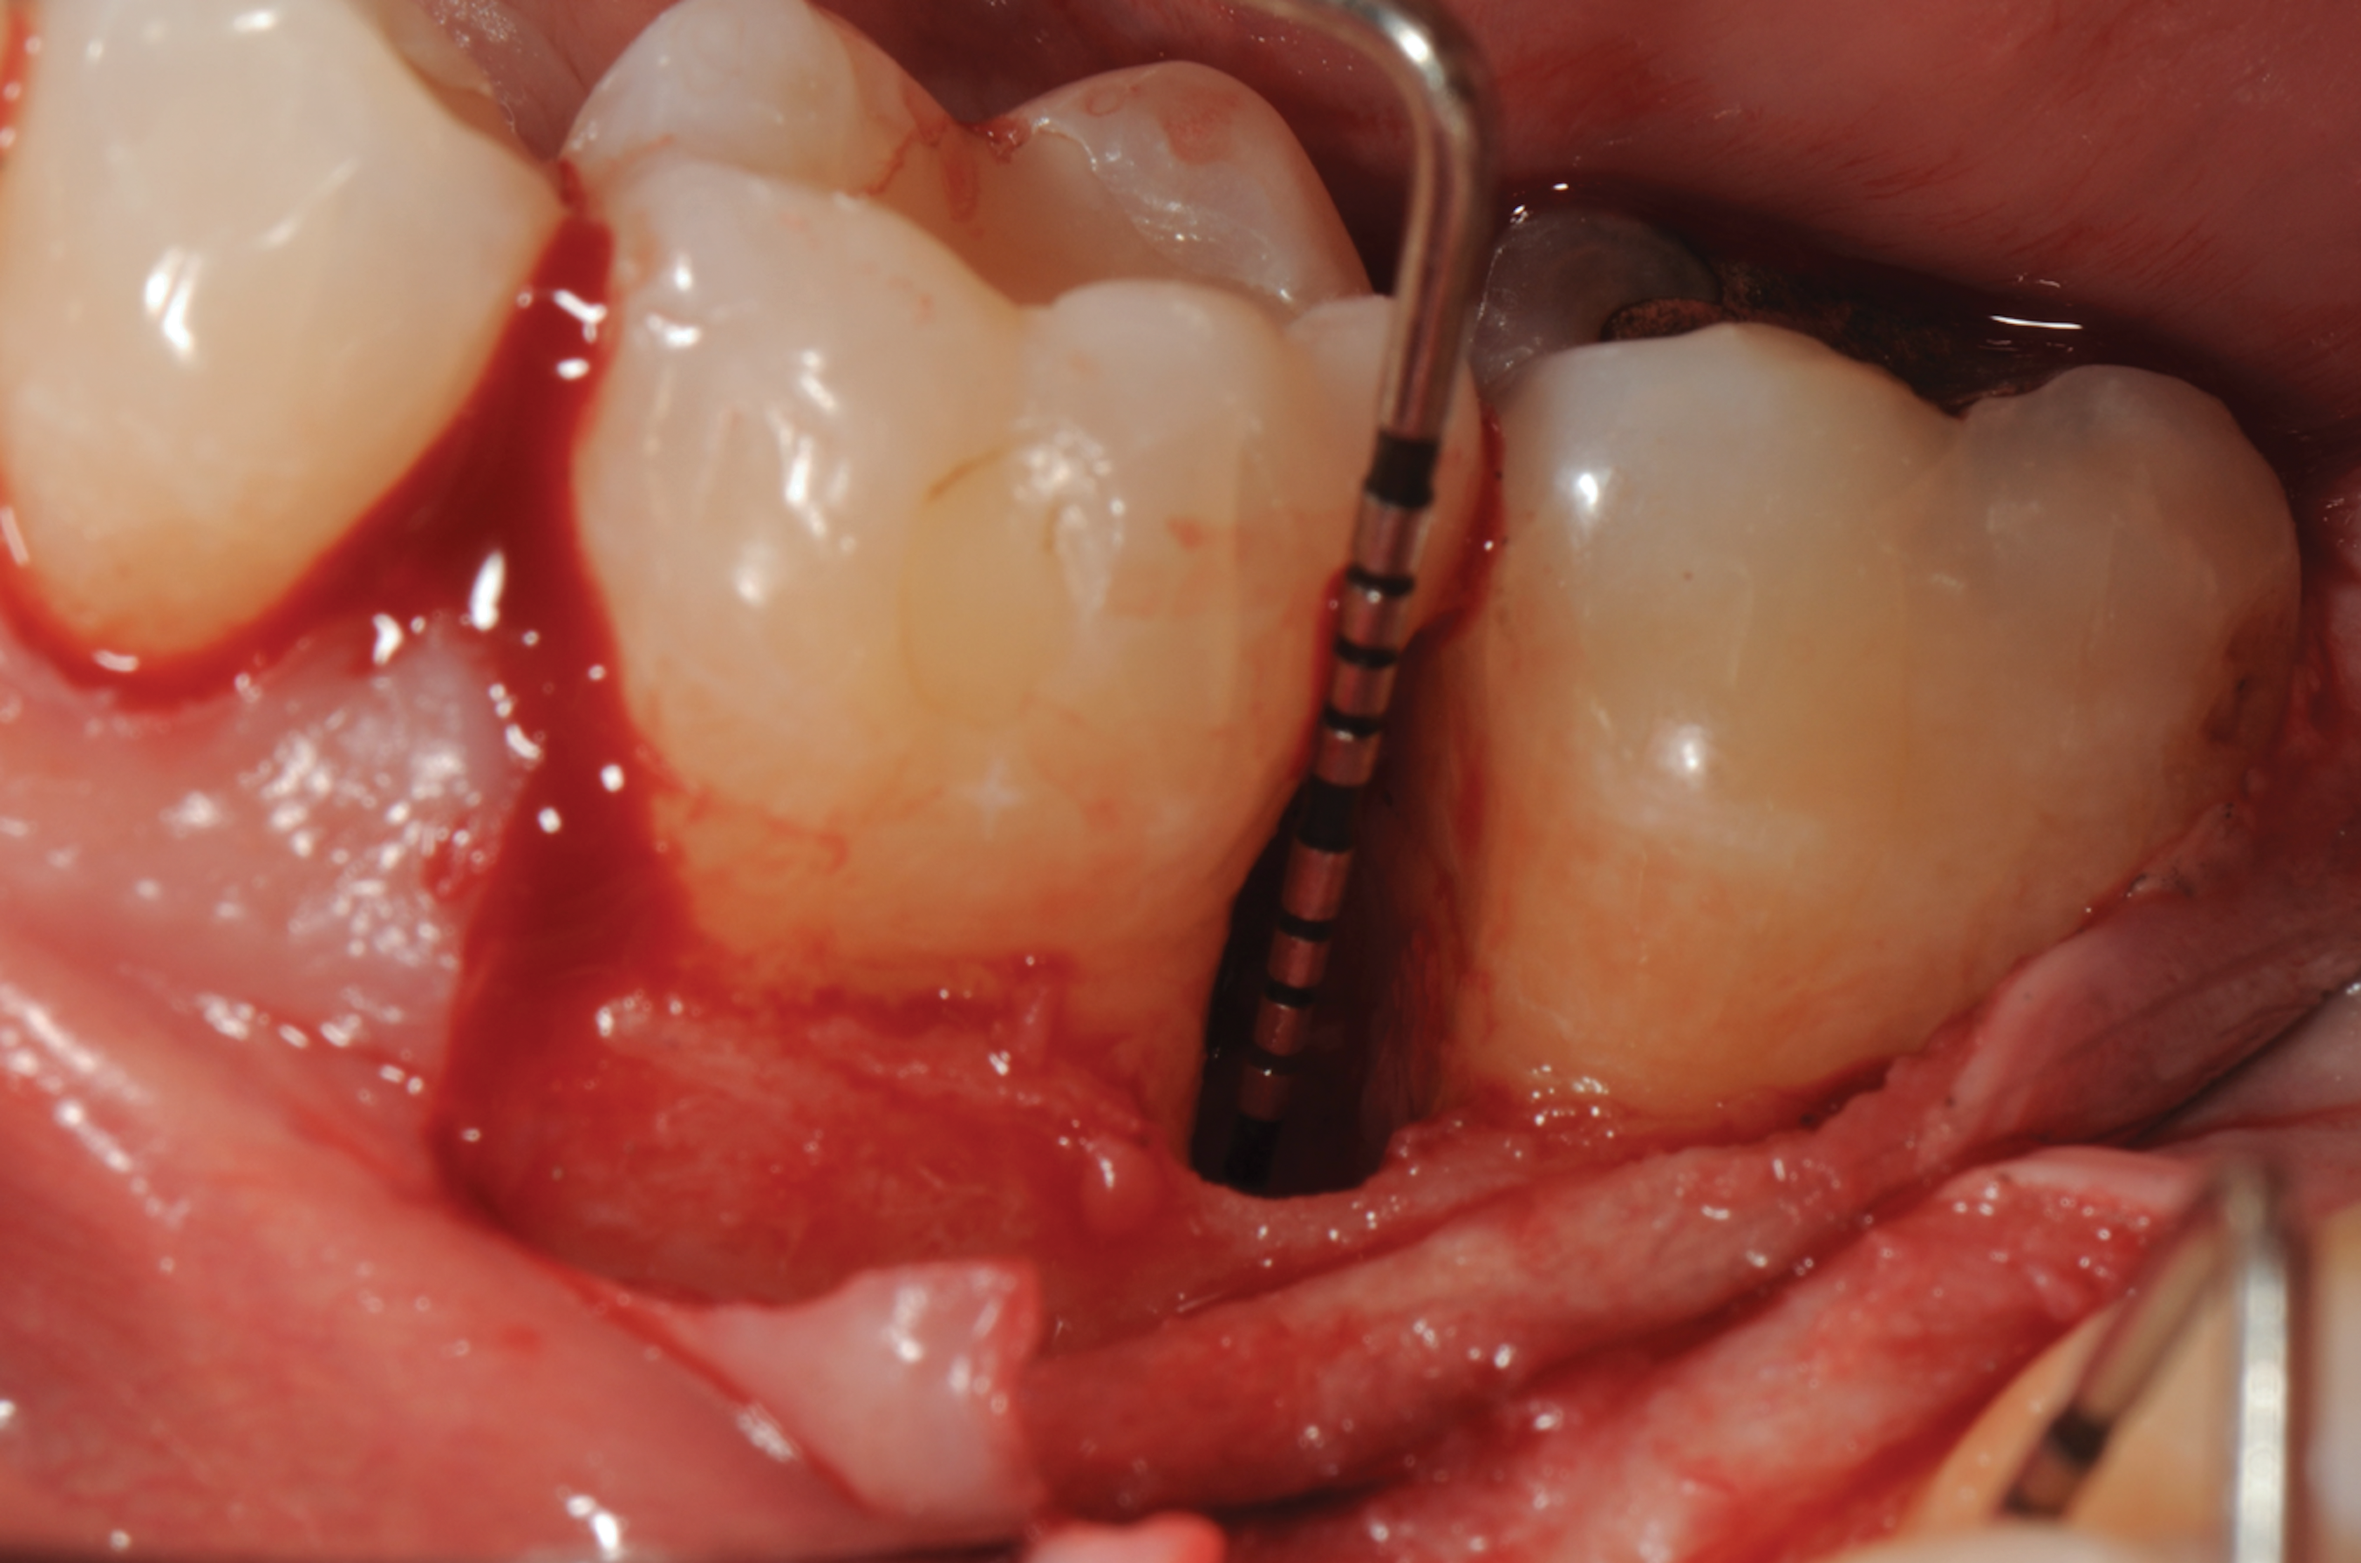

Fig 3. Distal probing depth of 10 mm at tooth No. 19.

Figure 3

Fig 5. Surgical access and root preparation. The flaps were elevated after intrasulcular incisions were made and a releasing incision was done in the mesial aspect of tooth No. 19. The granulation tissue was removed.

Figure 5

Fig 6. 5-mm-deep distal intrabony defect at tooth No. 19.

Figure 6